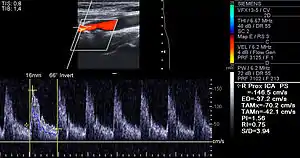

Examples of anatomical detection methods include coronary calcium scoring by CT, carotid IMT (intimal media thickness) measurement by ultrasound, and intravascular ultrasound (IVUS). Examples of physiologic measurement methods include lipoprotein subclass analysis, HbA1c, hs-CRP, and homocysteine. Both anatomic and physiologic methods allow early detection before symptoms show up, disease staging, and tracking of disease progression. Anatomic methods are more expensive and some of them are invasive in nature, such as IVUS. On the other hand, physiologic methods are often less expensive and safer. But they do not quantify the current state of the disease or directly track progression. In recent years, developments in nuclear imaging techniques such as PET and SPECT have provided ways of estimating the severity of atherosclerotic plaques.[78]